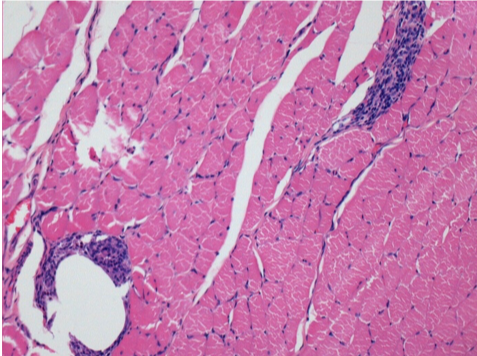

0,5 мл (5x 0,1 мл) підшкірна ін'єкція Ендопіл в праву підшкірну претибіальну ділянку.

Л:200x-Контроль-ПШ

П-10днів-ПШ-200X

П-30днів-ПШ-200X

П-90днів-ПШ-200X

П-210днів-ПШ-200X

П-210днів-ПШ-400X